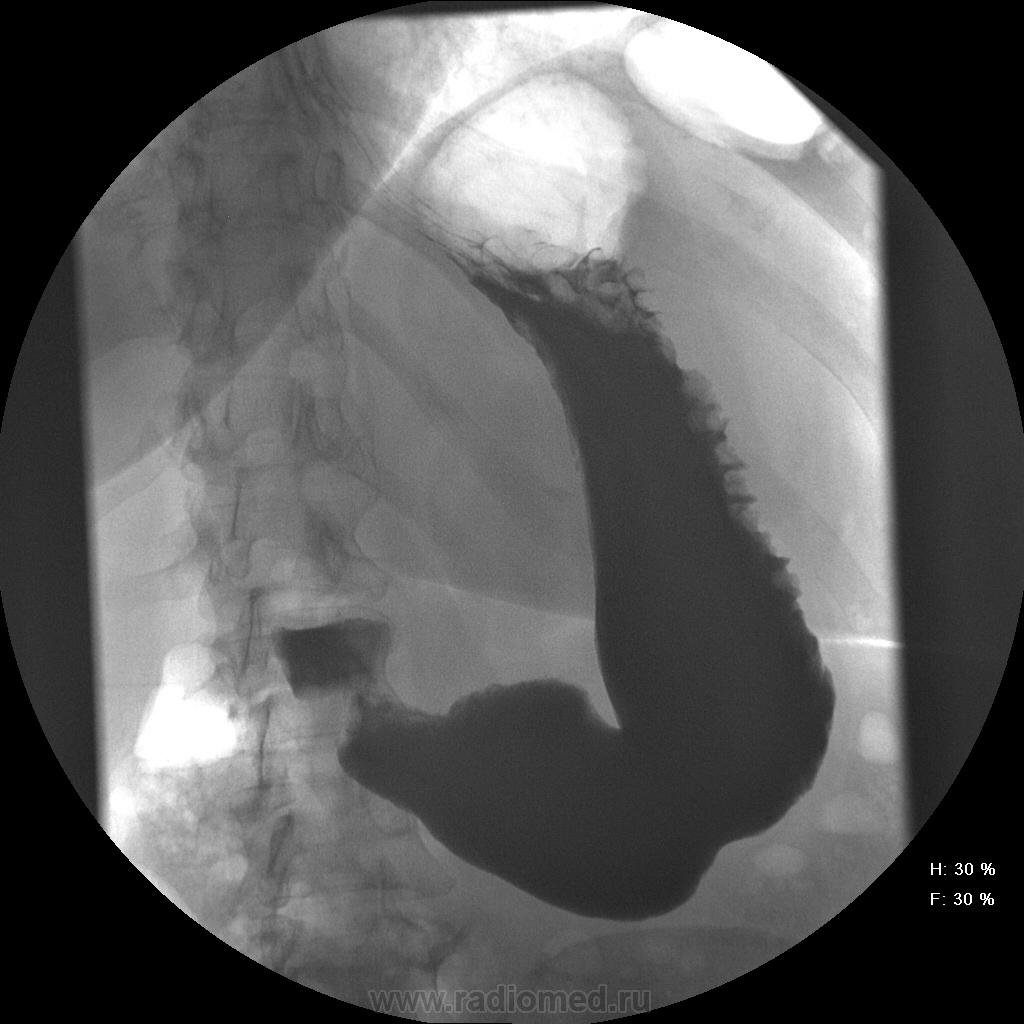

Женищина 49 лет, повышенного питания, обратилась с жалобами на потерю аппетита, жжение после чуть острой пищи, отрыжку с неприятным запахом, иногда темный стул, несколько похудела. Данные жалобы с сентебря-октября. Никуда не обращалась, коррегировала питанием. В последнее время стало хуже, обратилась...

Привратник удлиннен и ригиден, такое бывает при раке. Рек. ЭГДС.

Вы правы. я несколько недорасказал. женщина пришла уже с фгдс - инфильтративно-язвенный процесс в выходном отеде желудка у привратника по малой кривизне с переходом на переднюю стенку. так что прицельно смотрел этот отдел. перистальтка была ослаблена, краевой дефект в препилорической зоне по малой кривизне, передней стенке, кажущееся удлинение привратника, нависание основания луковицы - вообщем как в книжке. эвакуация было не изменена. написал рак выходного отдела желудка. вчера пришла гистология - высокодиф-я аденокарцинома. вот такая история.

Пока, касаясь только луковицы, но не препилорического отдела. "Ниши" в луковице есть, и они нуждаются в объяснении.

Конечно, в пилорическом канале уже растет, и "это" растет, уже и препилорической части и в луковице 12-ти перстной кишки.

И, рельф атипичный.